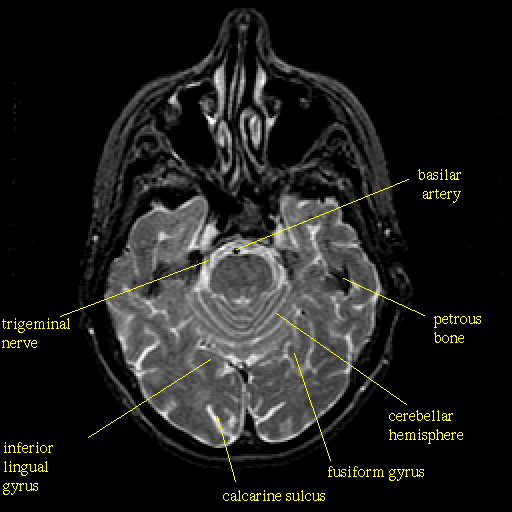

T2-weighted structural MR: Slice 17

Slice 17